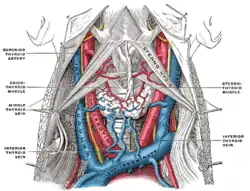

Arteria thyreoidea superior

Arteria thyreoidea superior (også kaldt øvre skjoldbruskkirtelarterie) er en arterie i halsen. Grenene af den øvre skjoldbruskkirtelarterie forsyner skjoldbruskkirtlen.

| Kilde | external carotid artery |

Hyoid artery Sternocleidomastoid artery Superior laryngeal artery Cricothyroid artery |

| Vene | superior thyroid vein |

| Forsyner | thyroid |